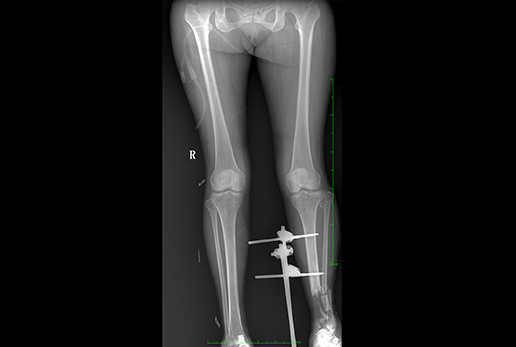

● 采用自主研發(fā)脈沖技術(shù),大尺寸動態(tài)平板,可實現(xiàn)動、靜態(tài)攝影模式無感切換,呈現(xiàn)更優(yōu)質(zhì)的圖像,為臨床醫(yī)生提供診斷依據(jù)。

● 集攝影、透視、造影等多功能為一體

● 核心優(yōu)勢: 大功率 動態(tài)平板 高清攝影 快速成像 透視造影 高清點片